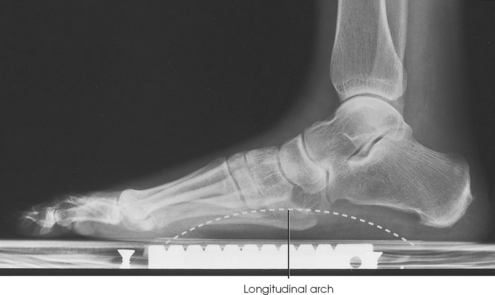

The bones of the foot are similar to the bones of the hand. Structural differences permit walking and support of the body’s weight. For descriptive purposes, the foot is sometimes divided into the forefoot, midfoot, and hindfoot. The forefoot includes the metatarsals and toes. The midfoot includes five tarsals—the cuneiforms, navicular, and cuboid bones. The hindfoot includes the talus and calcaneus. The bones of the foot are shaped and joined together to form a series of longitudinal and transverse arches. The longitudinal arch functions as a shock absorber to distribute the weight of the body in all directions, which permits smooth walking (see Fig. 6-2). The transverse arch runs from side to side and assists in supporting the longitudinal arch. The superior surface of the foot is termed the dorsum or dorsal surface, and the inferior, or posterior, aspect of the foot is termed the plantar surface.

Structures shown: The resulting image shows the entire foot in profile, the ankle joint, and the distal ends of the tibia and fibula (Figs. 6-51 and 6-52).

• Place the patient in the upright position, preferably on a low riser that has an IR groove. If such a riser is unavailable, use blocks to elevate the feet to the level of the x-ray tube (Figs. 6-53 and 6-54).

• If needed, use a mobile unit to allow the x-ray tube to reach the floor level.

• Place the IR in the IR groove of the stool or between blocks.

• Have the patient stand in a natural position, one foot on each side of the IR, with the weight of the body equally distributed on the feet.

• Adjust the IR so that it is centered to the base of the third metatarsal.

• After the exposure, replace the IR and position the new one to image the opposite foot.

Structures shown: The resulting image shows a lateromedial projection of the bones of the foot with weight-bearing. The projection is used to show the structural status of the longitudinal arch. The right and left sides are examined for comparison (Figs. 6-55 and 6-56).

SID: 48 inches (122 cm). This SID is used to reduce magnification and improve recorded detail in the image.